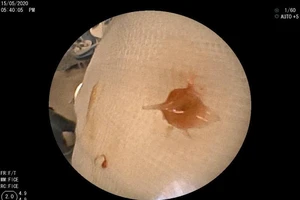

Bé 7 tháng tuổi hóc xương lươn gai sắc, tắc nghẽn phổi

19/05/2020 11:35